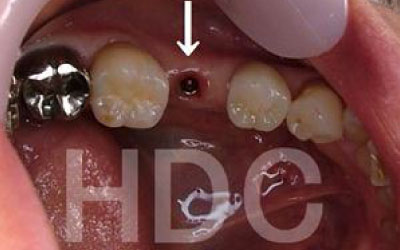

お口の状態や噛み合わせによって異なるため一概には言えませんが、一般的には奥歯が適しています。

特に、大臼歯(最も奥の歯)とその隣の歯がある部分です。

噛み合わせの力の60%以上がこの2本の歯で支えられているため、ここをインプラントでしっかり治療することは非常にお勧めです。